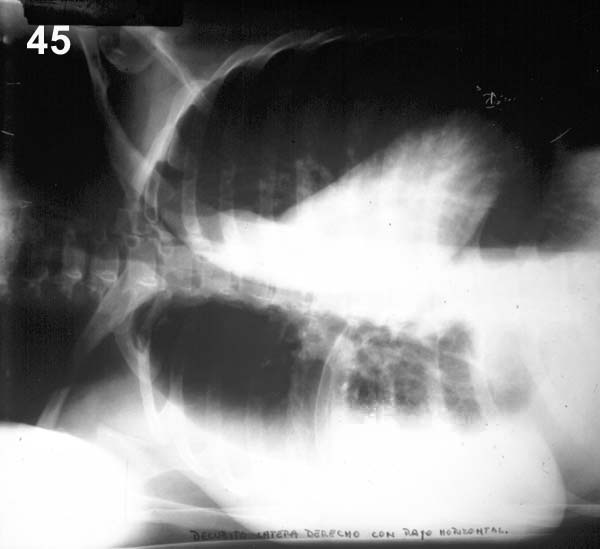

PLACA 45

En esta posición, el líquido que estaba acumulado entre pulmón y diafragma se desplaza, por efecto de la fuerza de gravedad, a la parte más baja de la cavidad pleural y se ve como una capa o franja homogénea de más o menos 2 cm de espesor sobre la pared costal derecha.